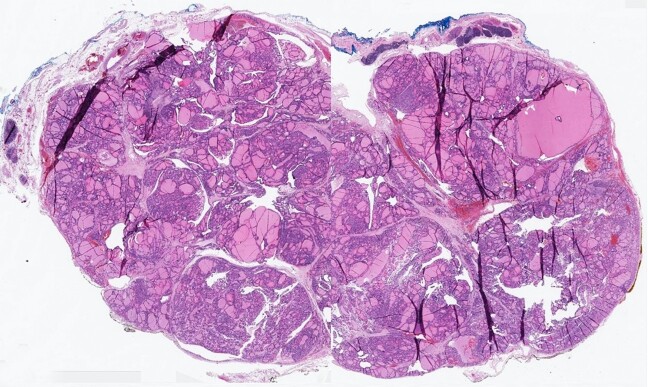

Ectopic thyroid tissue is rare in the general population and more prevalent in people who have existing thyroid disease. Common anatomical sites of ectopic thyroid tissue include the lateral cervical region, thyroglossal duct, mediastinum, lingual, sublingual, and submandibular region. Intrathymic ectopic thyroid tissue is exceedingly rare. The purpose of this report is to describe one such case in a 52-year-old African-American female with Graves' disease. The patient presented for a physical exam and follow-up. During the exam, an incidental mediastinal mass was discovered, which was evaluated by imaging studies and subsequently was resected. Histologically, the mass was composed of variable-sized thyroid follicles lined by a monolayer of cuboidal to columnar follicular epithelial cells and filled with eosinophilic colloid, surrounded by a rim of unremarkable compressed thymic tissue.